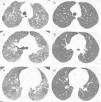

In the nine patients with a second HRCT scan, after a period treatment with corticosteroids and DMARDs of one to two years, a tendency of lowering in ground-glass score was observed (median [IQR]): (2.33 [2,3] vs. 2 [1.33–2.16]), P<0.056, along with lowering in CDAI score (27 [8–43] vs. 9 [5–12]), P<0.063 (Fig. 2).

Representative images of HRCT scan after and before treatment with prednisone and DMARDs. (A) Basal HRCT images, showing bilateral ground-glass images, centroliobular nodules and lobular areas of decreased attenuation. (B) There is a general improvement of the ground glass and no images of centroliobular nodules and lobular areas of decreased attenuation. The patient was treated with prednisone, methotrexate and sulphasalazine. There is a difference of 16 months between basal HRCT (A) and follow-up HRCT (B).